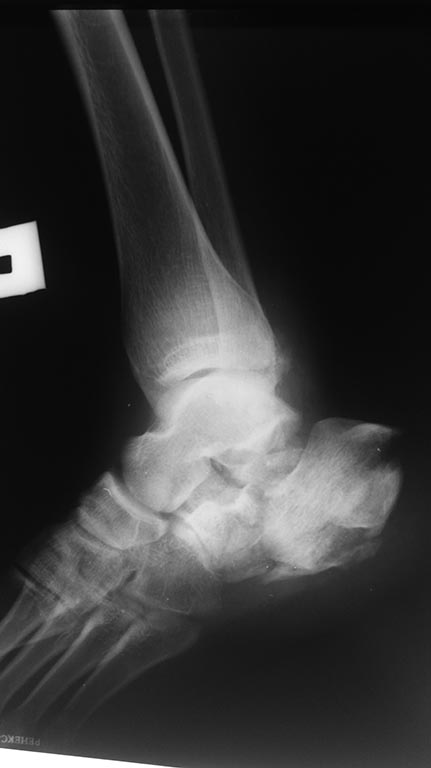

Уважаемый Бек, принципиально тут два варианта.

1) Леге артис - открытая репозиция остеосинтез пластиной. Тяжело, успешно в опытных руках, единственный способ восстановить суставную поверхность пяточной кости. К сожалению, высок риск осложнений, в первую очередь некроз кожи и, соответственно, инфекция.

2) Технически попроще - монтаж аппарата Голень стопа с дистальной тракцией бугра пяточно кости. Восстановит только угол Белера. Суставную поверхность не восстановит. Потом скорее всего потребуется подтаранный артродез.

Бек! Пациент тяжелый! Если местный статус спокойный, есть с дуга, то в операционной введите винт шанца в пятку свеху и как рычагом его низведите. На худой конец однозубым крючком книзу. Пока один держит под контролем С дуги несколько винтов как показали коллеги. Лодыжку я бы синтезировал стандартно, смещение более 2 мм. Конечно, надо бы пластинку на пятку, открыто, сустав восстановить.... один фиг они потом месяцами ( годами) мозг выносят, что болит. ( если ещё заживет первично). Только не спицами. По ним все сползет.